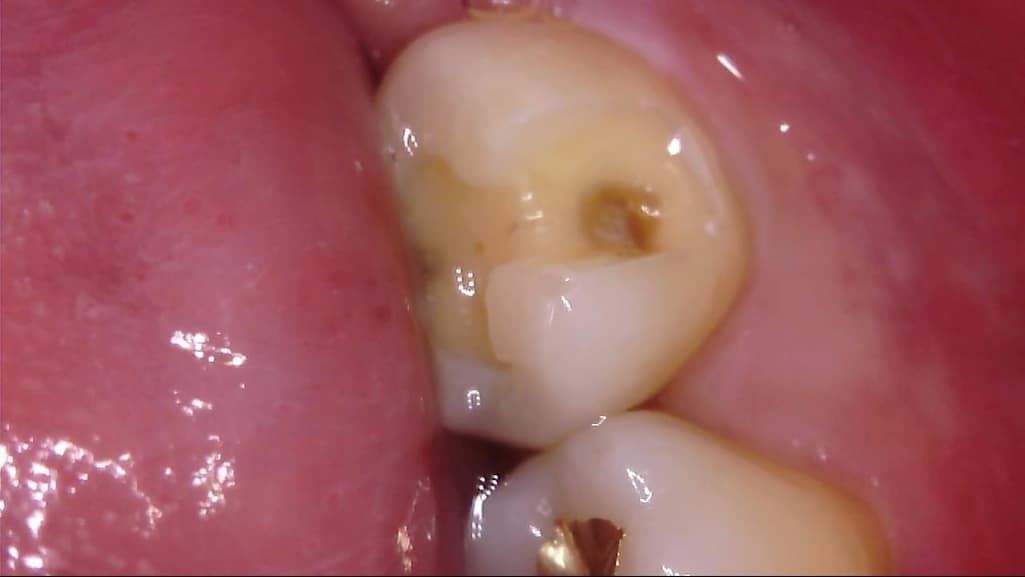

이차 우식이 상당히 깊게 발생하였는데, 치료 과정에서는 아래 사진과 같이 선생님께서 아래와 같이 일부 갈색 부분을 남긴 채 치아 삭제를 마치고 보철을 진행해 주셨습니다.

선생님께서는 "해당 부분은 착색 부위로, 이대로 덮어도 무방하다"라고 말씀 주셨고, 저 역시 더 이상 파고들어가면 신경치료가 예상되어 최선의 치료를 해 주셨다고 생각합니다.

다만 1) 해당 부위가 우식이 아닌 '착색'이 맞는지, 2) 해당 상태에서 보철물 안에서 추가 우식이 빠르게 진행될 가능성이 있는지, 3) 차라리 신경치료를 감수하고서라도 갈색 부분을 전부 없애는게 나았을지 불안감이 있는데, 관련하여 고견을 여쭙고 싶습니다.

사진에 보이는건 일단 착색과 2차 충치가 섞여 잇는거 같습니다. 충치를 제거하는 저스피드 기구로 제거를 해보기너 눌러 봐서 단단하면 충치가 아닙니다.

사진으로 보이는 부분은 충치에 어느정도 영향을 받은 부위는 맞습니다. 하지만 감염이 되어 있는것으로 보이지는 않습니다.

보철물로 치아를 씌우게 되면 해당부위에서 충치가 더 진행되거나 하지는 않습니다.

하지만 보철물의 경계부위에서 충치가 생길수 있기 때문에 보철물 주변은 꼼꼼하게 관리를 해주는것이 좋습니다.